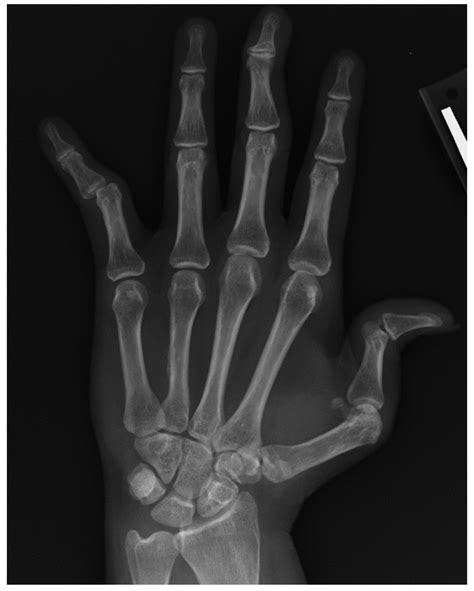

Radiography is the process of using radiation to view the internal structure of the body. It is a non-invasive procedure that allows doctors to see inside the body without surgery. The most common type of radiography uses X-rays, which are a form of electromagnetic radiation. When X-rays pass through the body, they are absorbed differently by various tissues. Dense tissues, like bone, absorb more X-rays and appear white on the image, while less dense tissues, like muscle and fat, absorb fewer X-rays and appear gray. Air-filled spaces, like the lungs, absorb the least amount of X-rays and appear black.

The history of radiography begins with the discovery of X-rays by Wilhelm Conrad Röntgen in 1895. Röntgen was experimenting with cathode rays when he noticed that a nearby fluorescent screen glowed when the cathode rays were turned on. He realized that an unknown type of radiation was causing the glow and named it X-rays. The first X-ray image, taken by Röntgen, was of his wife’s hand, showing her bones and a ring she was wearing. This groundbreaking discovery revolutionized medical imaging and led to the development of radiography as a diagnostic tool.

• Conventional Radiography: This is the most basic form of radiography, using X-rays to produce images on film or digital detectors. It is commonly used to diagnose fractures, pneumonia, and other conditions.

• Diagnostic Imaging: Radiography is primarily used for diagnostic purposes. It helps doctors identify fractures, infections, tumors, and other abnormalities. For example, a chest X-ray can reveal pneumonia, while a bone X-ray can show a fracture.